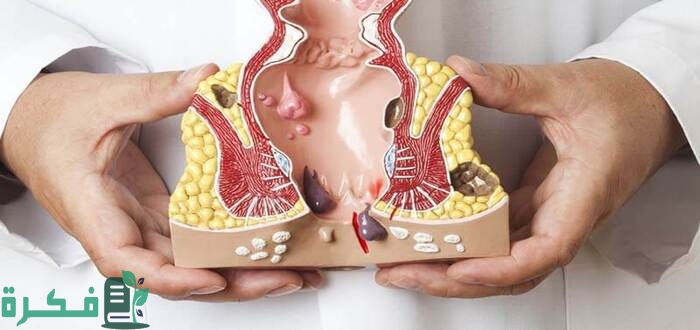

أكمل القراءة »تعرف معنا على أفضل 5 حبوب مسكنة للبواسير باعتبار أنه أصبح مرض مزمن في الفترة الماضية حيث أن عدد البالغين…